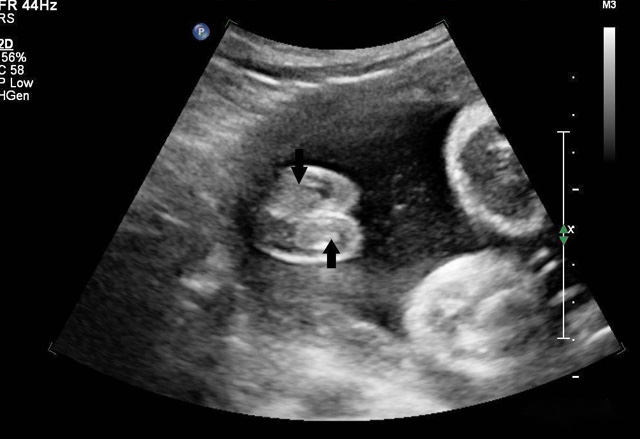

三維超聲技術(shù)可用于心臟、腹腔、婦科、產(chǎn)科、小器官、血栓、血管成像等多方面。